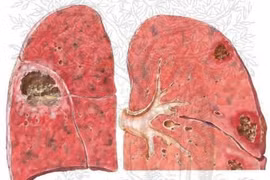

p xe phổi là tổn thương mưng mủ ở phổi rất dễ gây biến chứng nhiễm khuẩn huyết. Nếu không chữa khỏi có thể dẫn tới vỡ khối áp xe gây viêm màng phổi, màng tim, trung thất, hoại thư phổi…